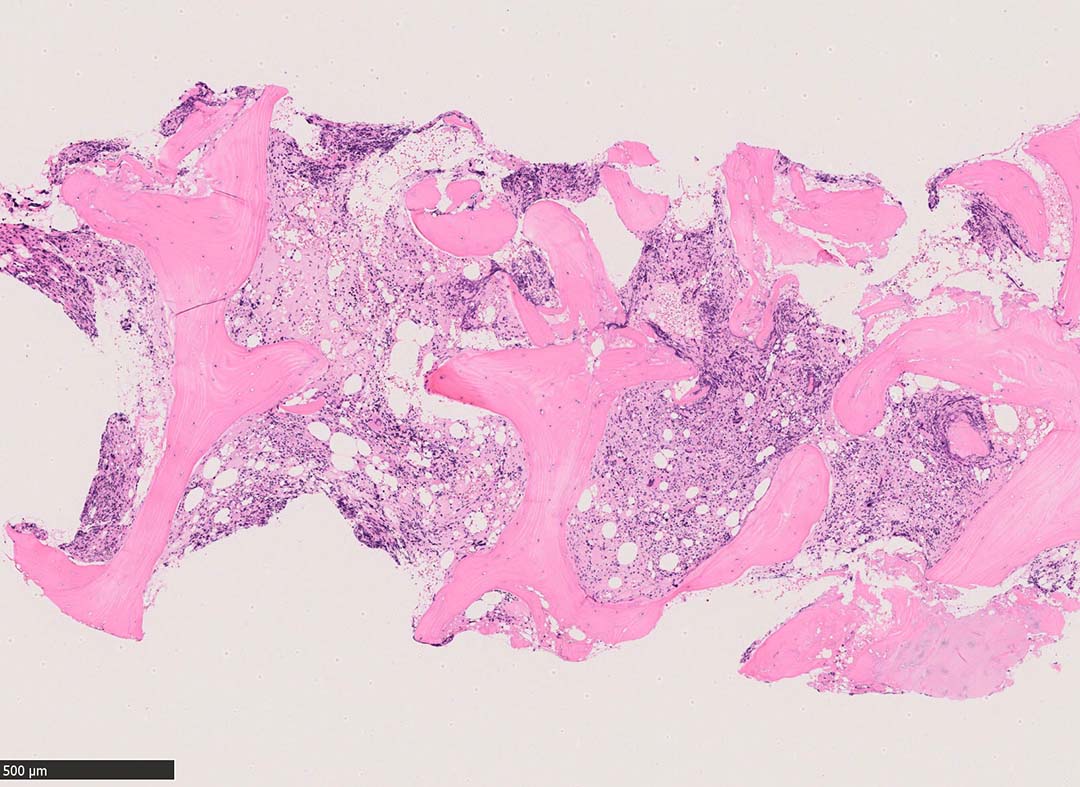

骨髄組織所見 bone marrow biopsy total 6mm in length

塗銀染色